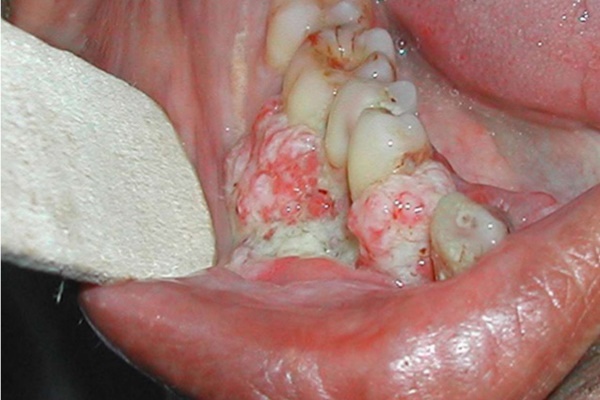

Khi nhìn thấy những nốt sùi, đốm lạ trong miệng lâu lành cần nghĩ đến ung thư khoang miệng

- U cục trong miệng: Một số trường hợp không bị đổi màu trong khoang miệng, không có vết loét mà xuất hiện u cục. Người bệnh có thể dễ dàng phát hiện bằng mắt thường hoặc sờ tay.

- Chảy máu trong khoang miệng: Chảy máu có thể tự nhiên hoặc sau khi va chạm nhẹ, sau ăn hoặc sau khi đánh răng.